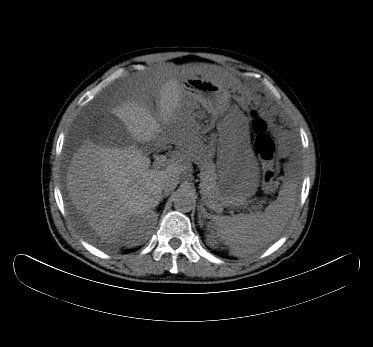

50 years male presented with huge abdominal swelling. This swelling started around 9 months back, gradually increasing and not getting relieved with anything. Image guided biopsy diagnosed the disease as mucinous carcinoma.

Peritoneum was lifted from abdominal wall. Approx 7 Liter mucinous fluid drained.